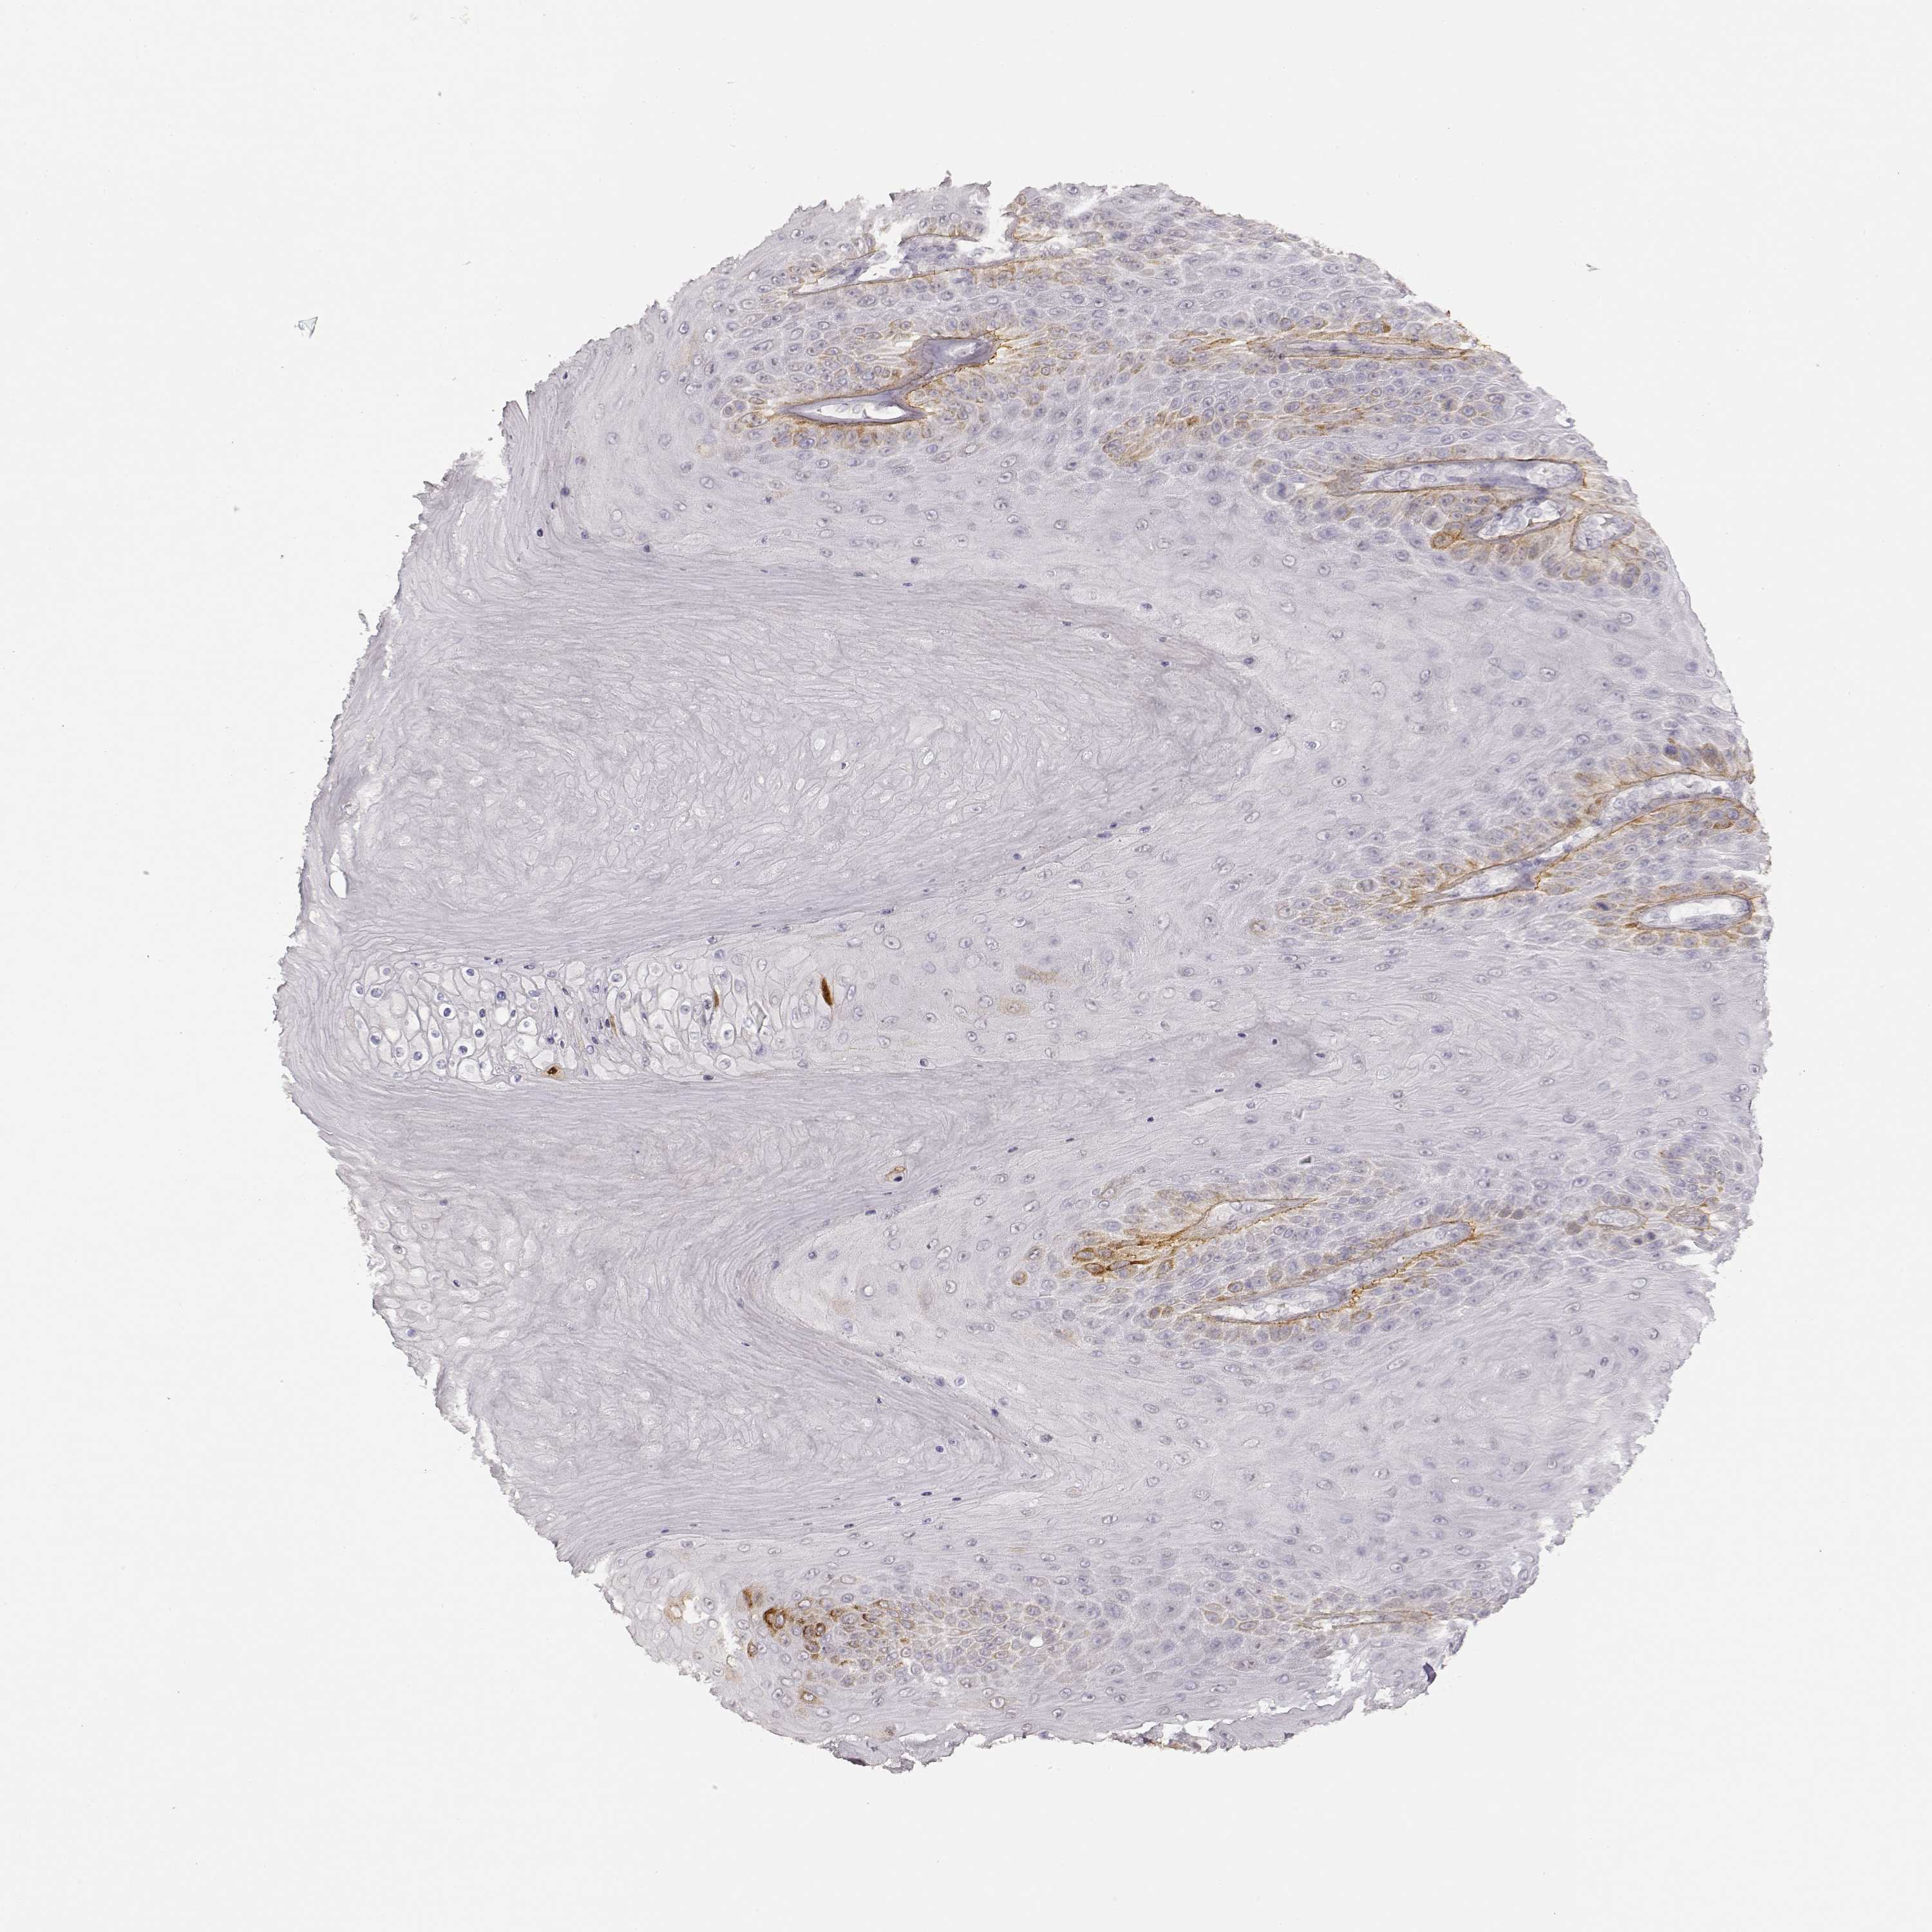

Basal cell and squamous cell cancer

SKIN CANCER - Protein expressioni

A mouse-over function shows sample information and annotation data. Click on an image to view it in a full screen mode. Samples can be filtered based on level of antibody staining by selecting one or several of the following categories: high, medium, low and not detected. The assay and annotation is described here.

Antibody stainingi

Antibody staining in the annotated cell types in the current human tissue is reported as not detected, low, medium, or high, based on conventional immunohistochemistry profiling in selected tissues. This score is based on the combination of the staining intensity and fraction of stained cells.

Each image is clickable and will lead to virtual microscopy that enables deeper exploration of all samples and also displays staining intensity scores, fraction scores and subcellular localization as well as patient and tissue information for each sample.

Antibody CAB004257

Antibody CAB078165

Basal cell carcinoma

Squamous cell carcinoma, NOS